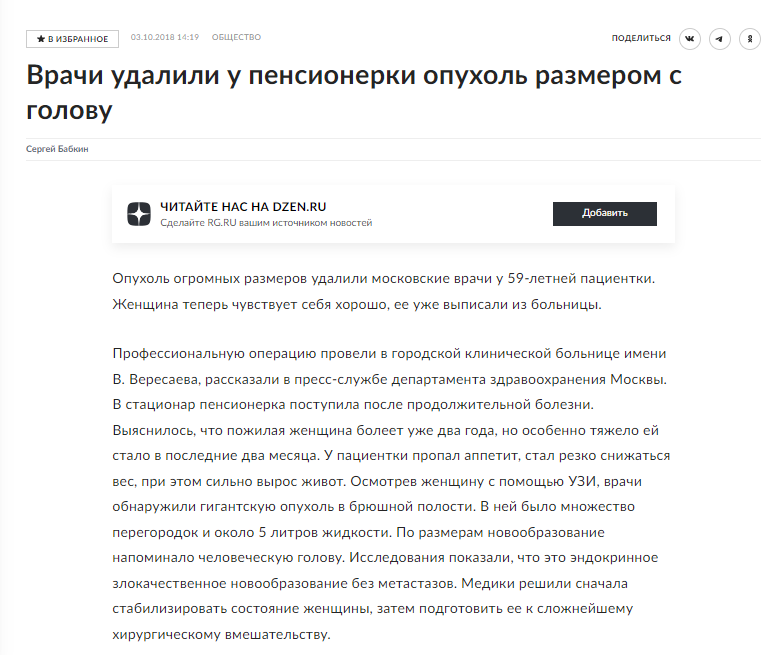

Можно вспомнить людей, обращающихся к онкологам с раком на последних стадиях и метастазами по всему телу. Спустя длительное время, после этапов «само пройдет» и «народная медицина поможет», человек обращается к врачу-специалисту. Но тот только разводит руками, предлагает обезболивание и какую-нибудь паллиативную помощь. А человек в этот момент кричит о том, что «врач рукожоп» и «наша медицина — говно».

Встречали такие публикации?

Я вижу их регулярно, но всегда им удивляюсь, ведь опухоли до такого размера вырастают не за месяц и не за два. Пишут, что болела 2 года (по факту, скорее всего дольше). Что мешало указанной пациентке обратиться раньше, дабы не доводить врачей до героизма, а журналюг — до публикации «уникального случая»? Ждала, что пройдет? Народная медицина не помогла, а Кашпировский больше не практикует?